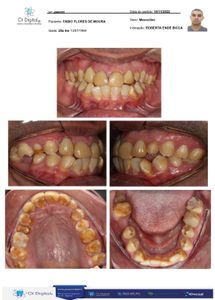

Minha mãe sempre teve problemas de convulsões dês de nova e tomava remédios muito fortes para conter estes espasmos e ficou grávida de mim e não sabia. Então continuou a tomar os remédios de convulsões e também fumava bastante e isto afetou todos os meus dentes fazendo eles nascerem com um esmalte extremamente fraco que dentro de um mês o esmalte era dissolvido ao escovar os dentes e isto fez com que eu fique apenas com a dentina da carga dentária que seria a estrutura amarelo forte do dente abaixo do esmalte, o nome desta doença é Hipoplasia. Eu sofri muito bullying no colégio por causa disto e fiquei com muitos traumas por tudo que já passei. A única coisa que pode me ajudar de acordo com o que os dentistas falam é desgastar todos os dentes e por coroas em resina para corrigir a deficiência de esmalte. Mas custa num total de. R$ 32.900,00 para fazer esta reabilitação. Minha mãe é analfabeta... E sou eu quem estudou e trabalhou para poder dar uma vida digna para ela e retribuir um pouco por todo o sacrifício que ela fez por mim. Pois meu pai não quis me assumir e nunca ajudou a me criar. Largou a minha mãe antes de eu nascer!